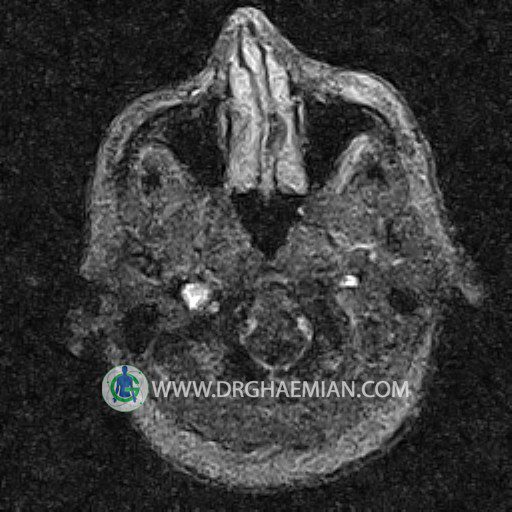

ام آر وی یک روش تصویربرداری دقیق و غیر تهاجمی است که برای معاینه ورید های بدن و ارزیابی سلامت رگ ها استفاده می شود. ورید ها خون را از اعضای بدن به قلب باز می گرداند تا دوباره اکسیژن و مواد مغذی به خون داده شود. ام آر وی جریان خون را ارزیابی و موارد غیرعادی مضر مانند لخته های خونی را شناسایی می کند. در این کیس ترومبوز دیواری مغز در سینوس عرضی راست و ترمبوز جزئی در سینوس عرضی چپ دیده می شود.

– Narrowing of left transverse sinus with filling defect & inthimal irregularity

suggestive for partial thrombosis

– Inthimal irregularity in anterior wall of right transverse sinus suggestive for mural thrombosis

are seen